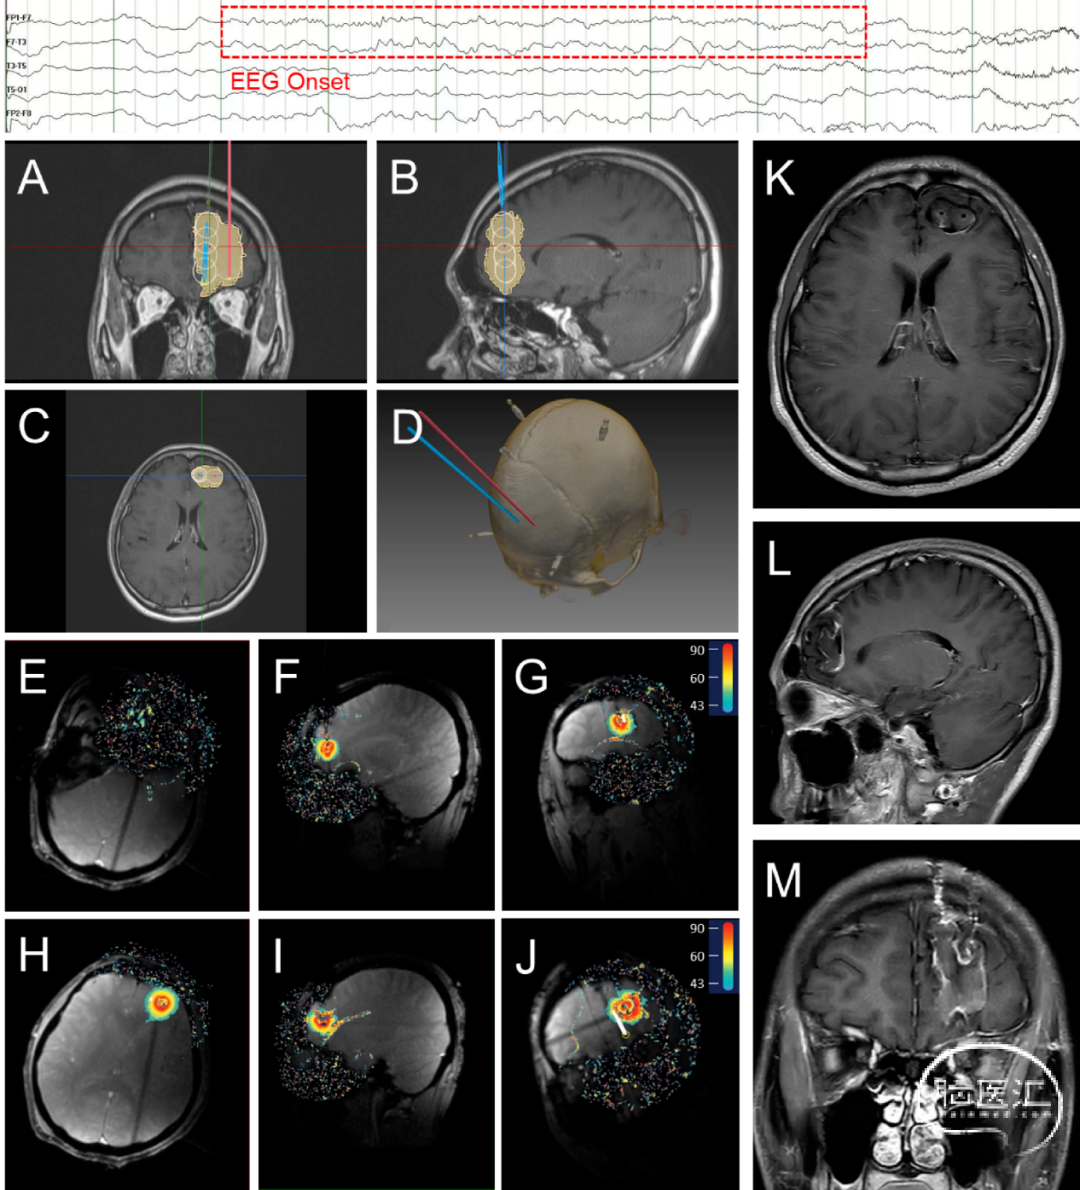

术前使用立体定向手术计划软件(V1.0,佳量医疗科技有限公司,中国,杭州)计划靶点位置、大小和光纤轨迹,以产生临时靶点坐标。所有手术均在全麻下完成,运动Leksell立体定向框架或神经外科机器人进行立体定向手术。切开皮肤,用电钻钻取颅骨,然后电凝烧灼硬脑膜。固定颅骨骨锚,计算电极插入深度,硬质清洁棒破入脑内建立通道后,依次插入并固定两根激光光纤。患者术中磁共振线圈固定后,移入术中磁共振室,接受初始术中MRI(Discovery MR750w 3.0T,GE Medical System,US)扫描,以检查光纤的准确定位,相关操作步骤如图1所示。

所有消融均使用LaserRO™MRI引导激光消融系统(Genlight Inc,Hangzhou,Zhejiang,China)进行,包括术前计划和术中消融。术前计划包括将消融手术计划(目标和轨迹信息、消融参数计划)输入手术平台。术中手术基于消融平台、光纤套件和手术工具,使用来自MR设备的实时图像进行治疗。系统通过冷却模块向光纤探头输出冷却水。在整个治疗过程中,消融平台采集实时图像,检测靶区及其周围组织的温度,确保安全有效的消融,相关消融过程如图2–4所示。

LaserRO™系统在设计中具有独特的技术规格。在主要性能方面,它采用了980nm和1064nm双波长光源,最大激光功率可达15W。探头有两种外径:1.55mm和2.3mm,三种不同的扩散尖端长度:4mm、10mm和15mm。冷却系统提供实时流量和残留物监测。插入式光纤探头兼容1.5T和3.0T MRI环境,MRI温度检测间隔为3.5秒,测温精度为±2°C。